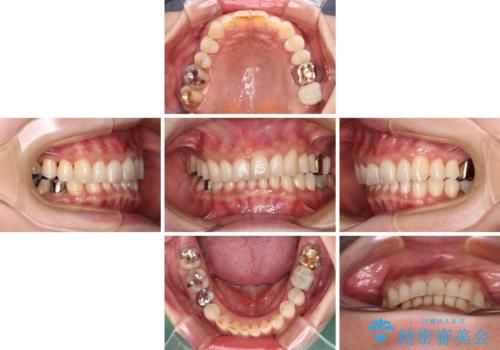

デコボコの歯とむし歯 インビザライン矯正治療とむし歯治療

- 奥歯が咬めないくらいに痛いとのことで来院された患者様です。

痛みの強い歯は、歯髄組織が強い炎症を起こしており、神経を取り除く必要であったため、速やかに根管治療を行いました。

その後、オールセラミッククラウンにて補綴治療を行う予定でしたが、処置した歯以外にも治療が必要と思われる歯があったり、デコボコした歯列も気になるとのことで、患者様希望によりインビザラインにてマウスピース矯正を行うこととしました。

まずは矯正治療前に必要なむし歯処置を行い、その後矯正治療を行ってから、最後にオールセラミッククラウンなどで補綴治療を行うこととしました。

咬合力が非常に強く、全体的に歯が擦り減っている状態であったので、理想的な咬み合わせを達成することは難しく、また咬合力が強い方のマウスピース矯正は、思い通りに動かないことがあるため、ワイヤー矯正の方が望ましいように思えました。

治療途中で2年強、体調を崩されて通院ができなくなってしまったため、必ず通院が必要なワイヤー矯正ではなく、マウスピース矯正で結果的には無事に治療を終えることができました。